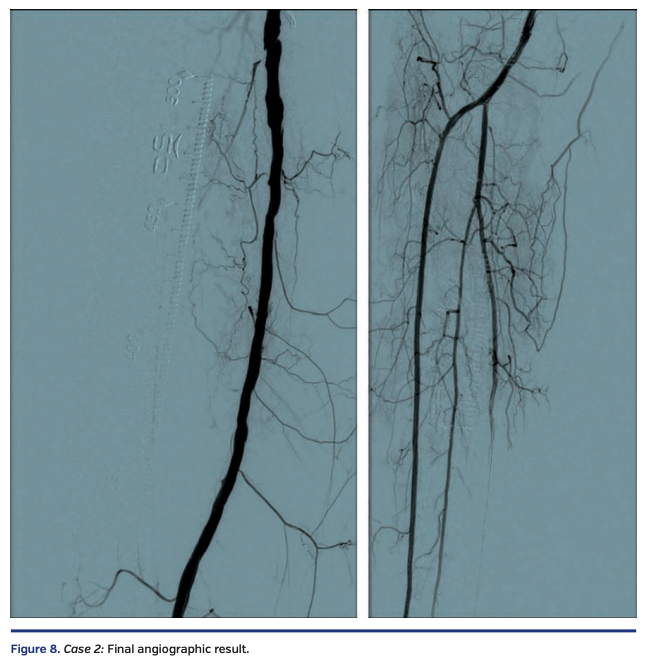

Sequential balloon angioplasty in the anterior tibial artery was performed with 2.0 mm and 4.0 mm Coyote balloon (Boston Scientific). Kissing balloon angioplasty of the popliteal artery, proximal anterior tibial, and tibioperoneal trunks was performed with long 3 mm balloons, followed by drug-coated balloon angioplasty of the right femoropopliteal segment with a 6 mm x 250 mm IN.PACT Admiral drug-coated balloon (Medtronic). There was restoration of normal flow in all treated segments (Figure 8), with a warm foot and a palpable dorsalis pedis artery at the end of the case.